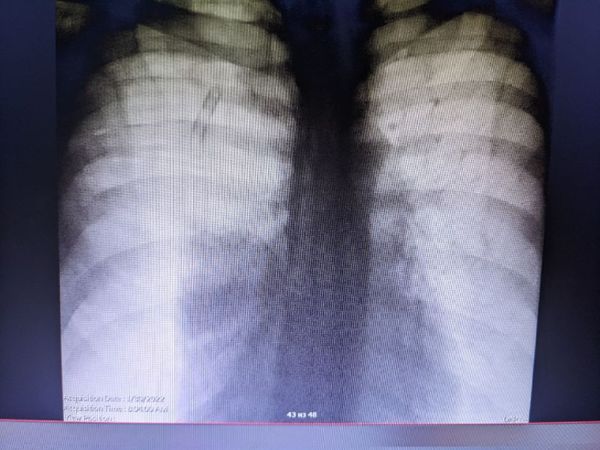

Рентгенография органов грудной клетки при поступлении 28 января выявила правосторонний пневмоторакс, лёгкое при этом уменьшилось, спало и не участвовало в дыхании. В правом лёгком также обнаружили скопление воздуха (подкожную эмфизему).

Рентгеноскопия от 2 февраля показала расправление правого лёгкого, дренаж правой плевры и подкожную эмфизему правой половины грудной клетки.

По результатам исследования от 4 февраля эмфизема начала уменьшаться, левое лёгкое без изменений, диафрагма в обычном расположении.